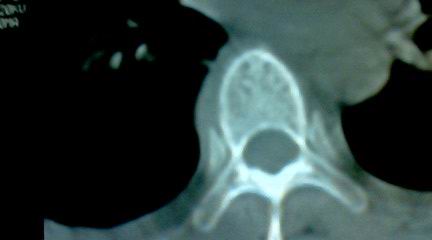

标题: CT25218:请教!胸部CT,胸8椎体骨质破坏,伴周围软组织肿。 [打印本页]

标题: CT25218:请教!胸部CT,胸8椎体骨质破坏,伴周围软组织肿。

患者,女41岁,肢体乏力。

两肺上叶继发性肺结核;胸椎结核并椎旁寒性脓肿形成。

胸椎结核并椎旁寒性脓肿形成。